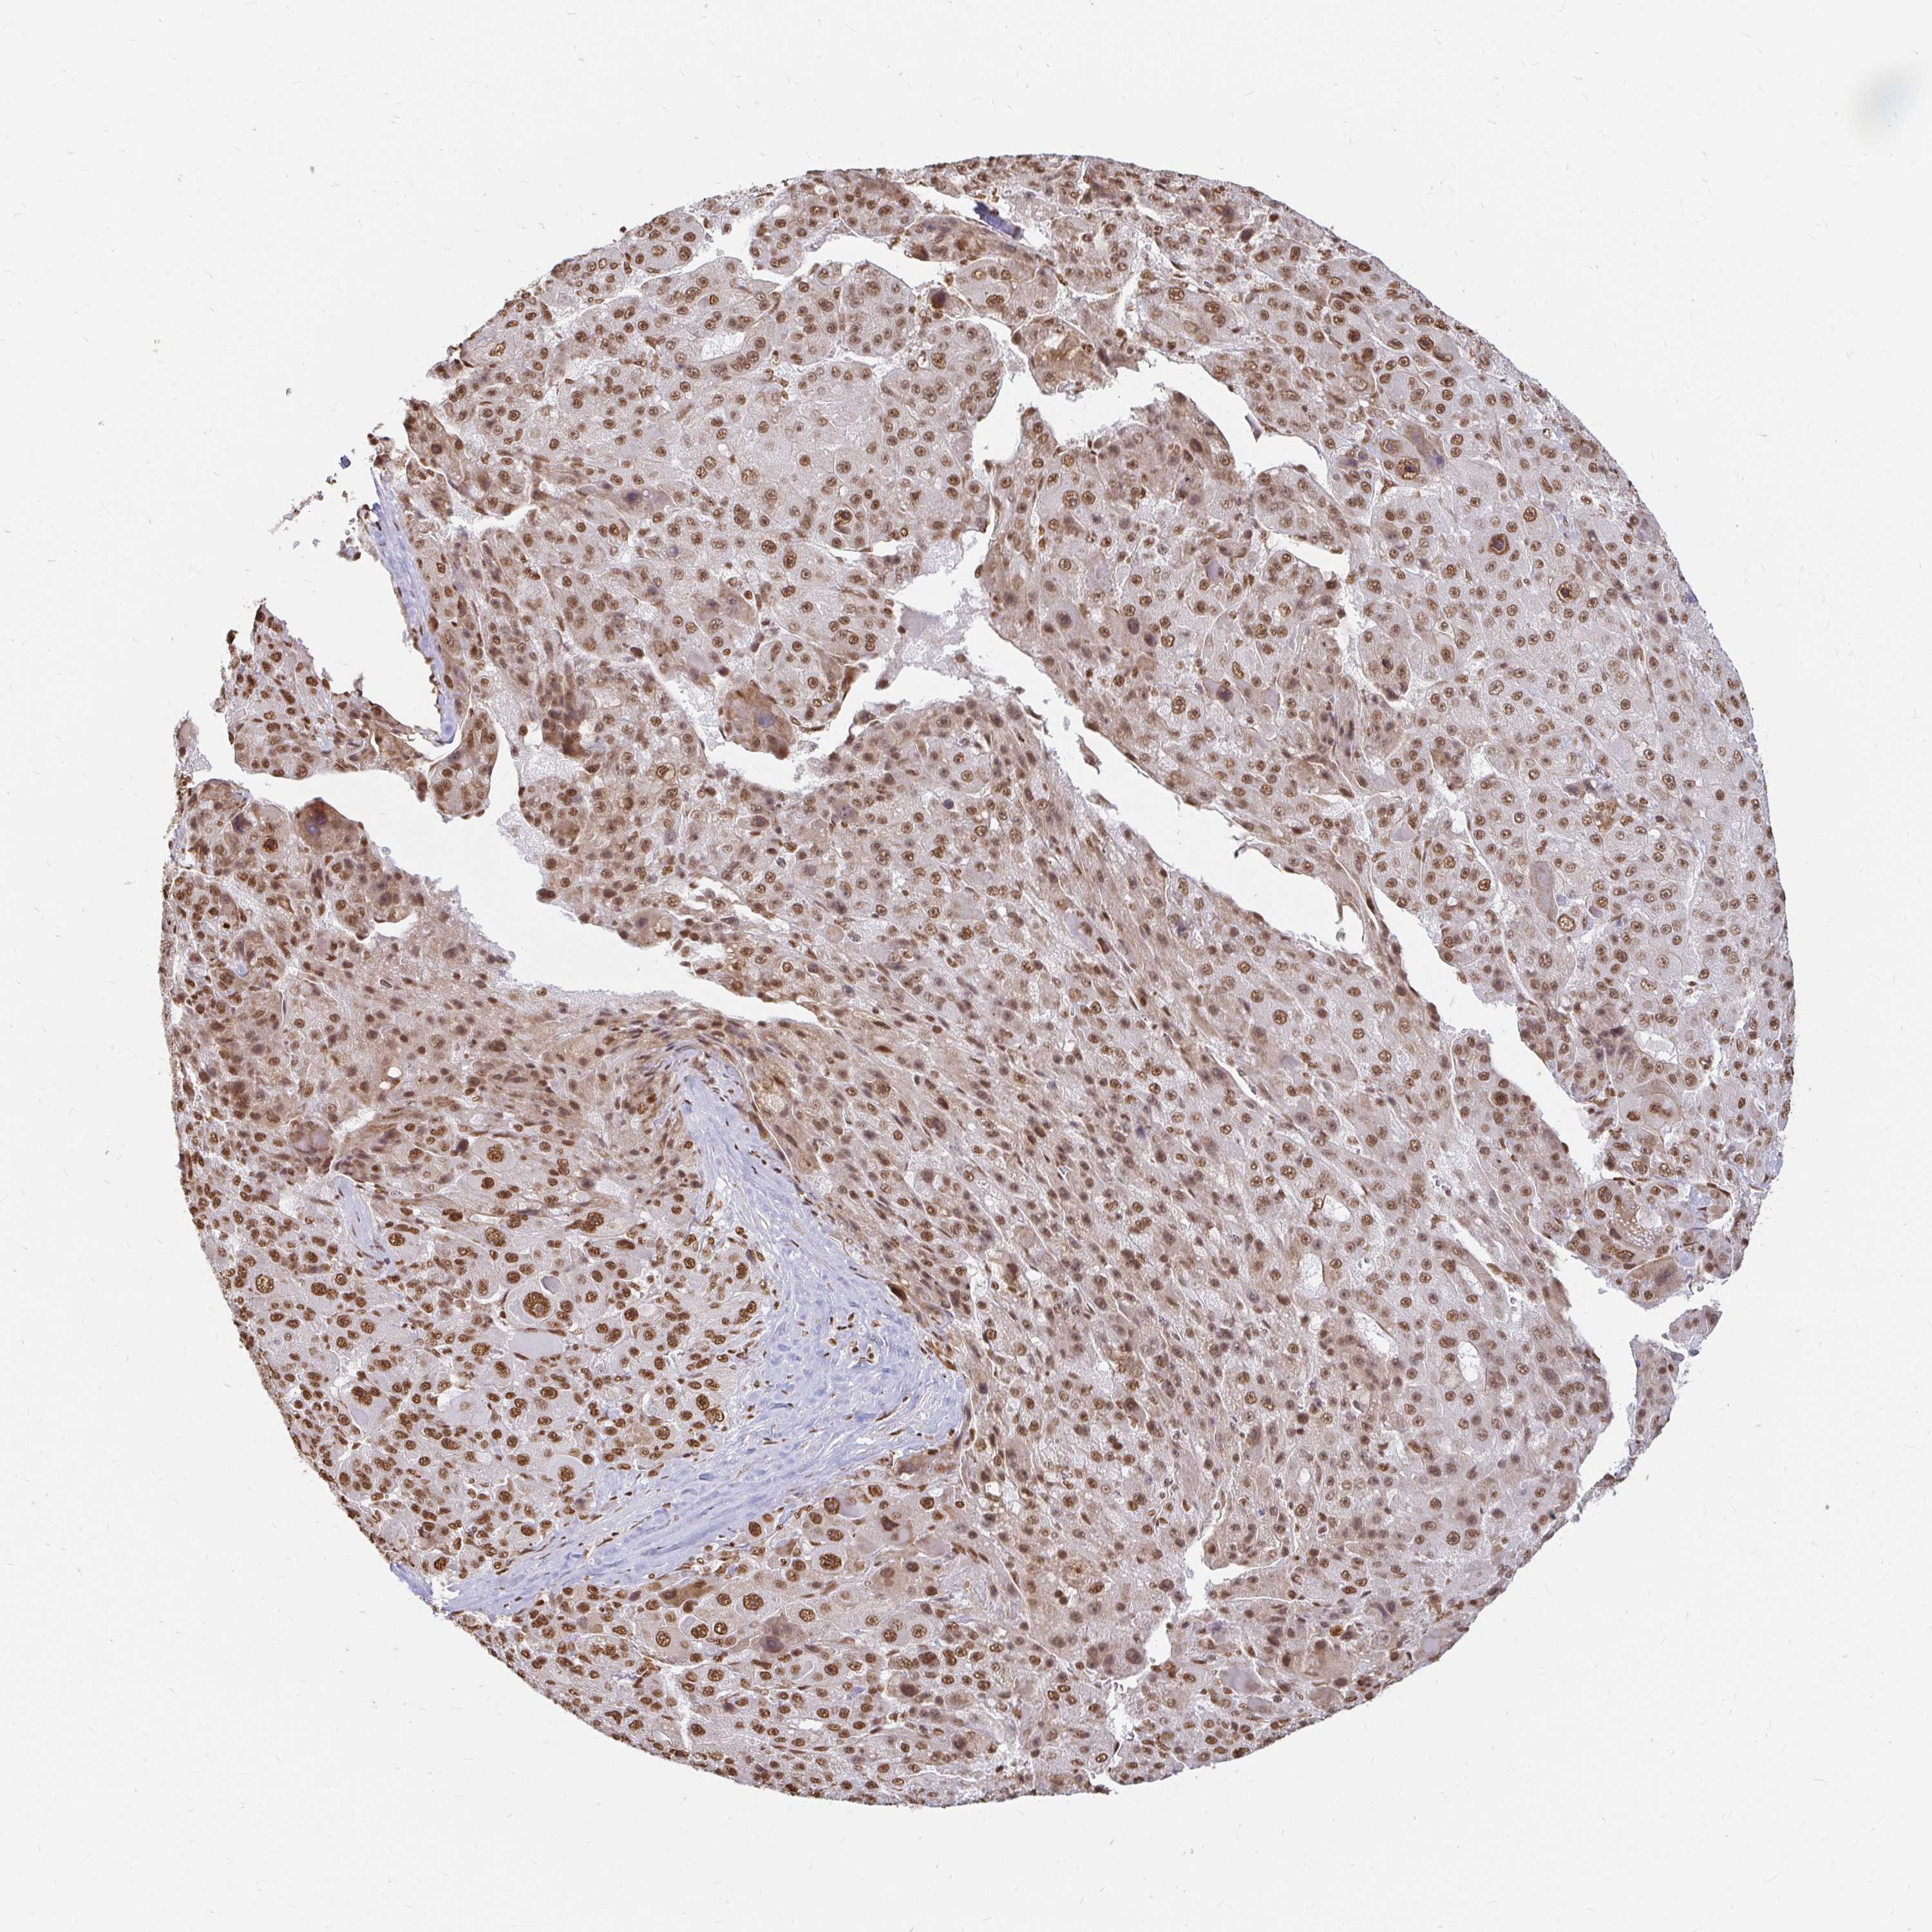

LIVER CANCER - Protein expressioni

A mouse-over function shows sample information and annotation data. Click on an image to view it in a full screen mode. Samples can be filtered based on level of antibody staining by selecting one or several of the following categories: high, medium, low and not detected. The assay and annotation is described here.

Note that samples used for immunohistochemistry by the Human Protein Atlas do not correspond to samples in the TCGA dataset.

Antibody stainingi

Antibody staining in the annotated cell types in the current human tissue is reported as not detected, low, medium, or high, based on conventional immunohistochemistry profiling in selected tissues. This score is based on the combination of the staining intensity and fraction of stained cells.

Each image is clickable and will lead to virtual microscopy that enables deeper exploration of all samples and also displays staining intensity scores, fraction scores and subcellular localization as well as patient and tissue information for each sample.

Antibody HPA041057

Antibody HPA058707

Antibody CAB011532

Staining

High

Medium

Low

Not detected

Intensity

Strong

Moderate

Weak

Negative

Quantity

>75%

75%-25%

<25%

None

Location

Nuclear

Cytoplasmic/membranous

Cytoplasmic/membranous,nuclear

Cholangiocarcinoma

Carcinoma, Hepatocellular, NOS